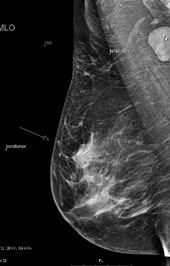

MARI klier